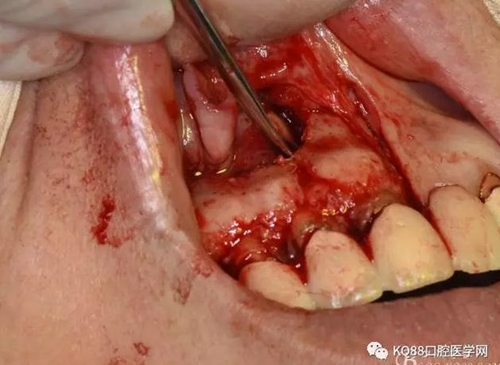

圖11.摘除囊壁后形成的骨腔

圖12.超生骨刀切除12根尖